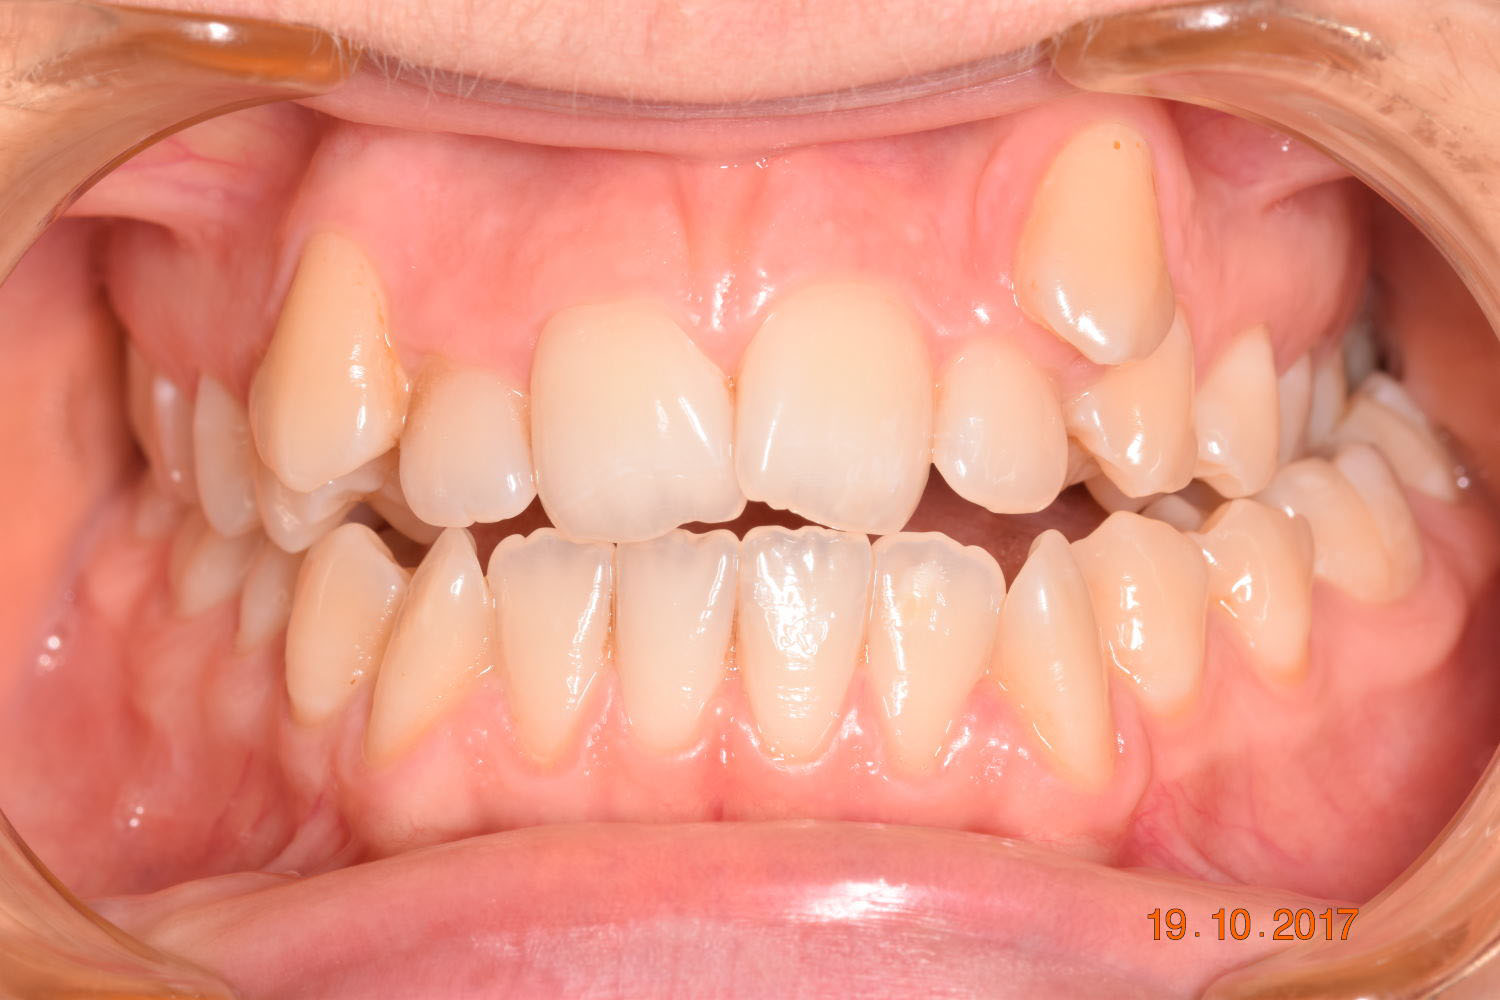

Adhering to the principles of Face First Orthodontics, the primary objective was to increase midface support by expanding the upper maxilla, fixing the cross bite, and aligning the teeth. Closing the open bite was a secondary objective.

The facial changes are impressive considering treatment involved only conventional orthodontics and not orthopedic interventions, TADs, or surgery.

Dr. Coca concludes that improved biomechanical understanding of extreme crowding and torque management could have reduced treatment duration. From his experience, proper force management can facilitate bone remodeling, challenging the idea of bone limitations in orthodontics.

Correcting muscle behavior during swallowing and in the passive state is key to solving open bite and crossbite as well as ensuring lasting stability of treatment outcomes.